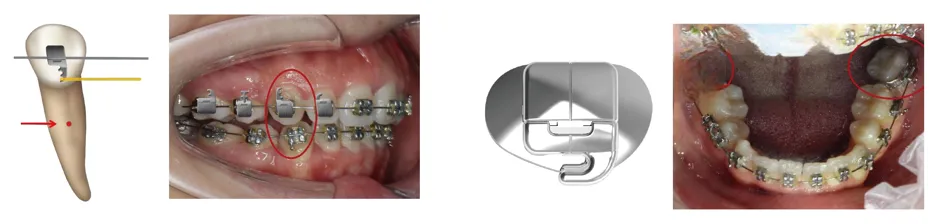

02、控轴能手

控根作用,矫治力更靠近阻力中心、更方便控根

更早实现第二磨牙控制,创新性粘贴式第二磨牙